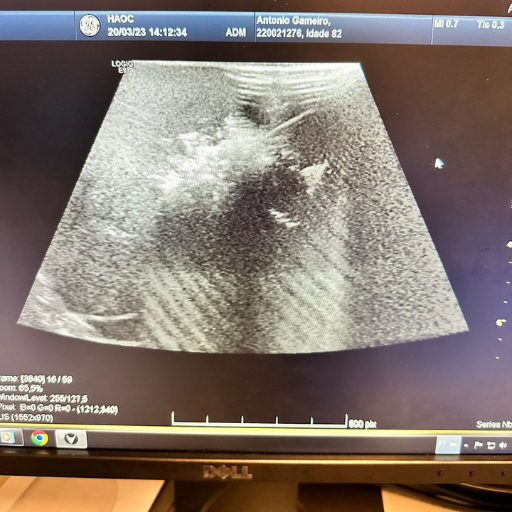

Guiados por imagens em tempo real, os procedimentos são realizados com alta precisão, diretamente no local a ser diagnosticado e/ou tratado.

Técnicas como radioablação e crioablação para destruir tumores primários e metastáticos com precisão, minimizando danos ao tecido saudável.